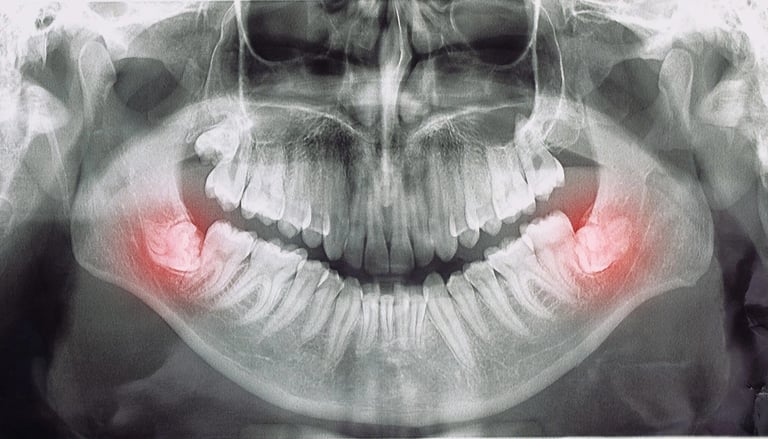

1️⃣ Valoración clínica y diagnóstico de la complejidad de cada muela. (Radiografia Panoramica) apoya el diagnostico.

Cuando la cordal está incluida, en mala posición o cerca de nervios, la valoración y el procedimiento se realizan con cirujano maxilofacial, experto en cirugías complejas y controladas.